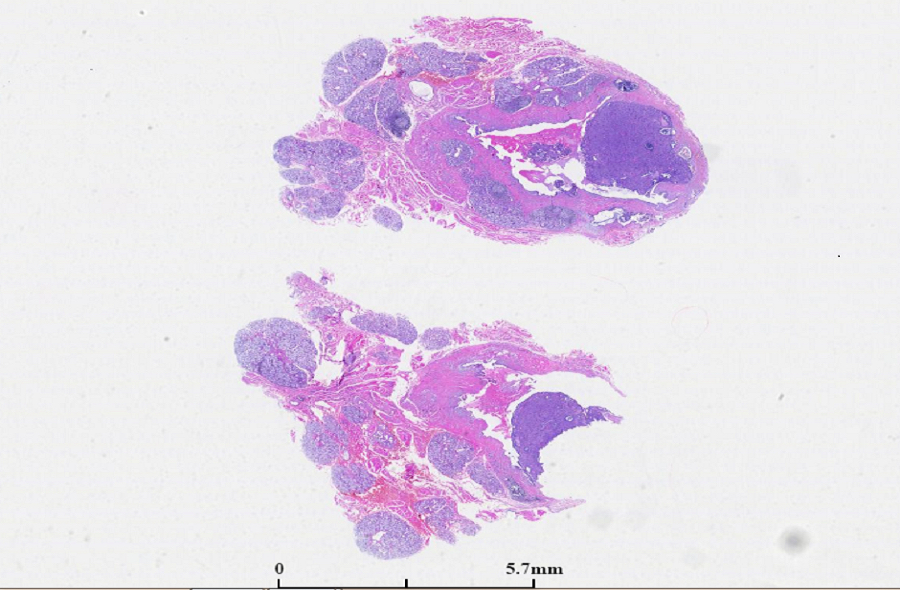

2. 肿瘤边界清楚或边缘有浸润,褐色、白色和粉红色。

1. 有学者根据形态学特点将黏液表皮样癌进行分级:低度恶性肿瘤大体为境界清楚的肿块,囊实性。镜下见大量分化良好的黏液细胞。高度恶性肿瘤多呈实性,其生长具有侵袭性。以鳞状细胞和中间型细胞为主要成分,产黏液细胞较少。也有学者对肿瘤进行评分,根据评分分级(见附表)。